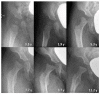

Mucolipidosis type II (MLII) is a rare lysosomal storage disorder caused by defective trafficking of lysosomal enzymes. Severe skeletal manifestations are a hallmark of the disease including hip dysplasia. This study aims to describe hip morphology and the natural course of hip pathologies in MLII by systematic evaluation of plain radiographs, ultrasounds and magnetic resonance imaging (MRI). An international two-centered study was performed by retrospective chart review. All MLII patients with at least one pelvic radiograph were included. A total of 16 patients were followed over a mean of 3.5 years (range 0.2-10.7 years). Typical age-dependent radiographic signs identified were femoral cloaking (7/16), rickets/hyperparathyroidism-like changes (6/16) and constrictions of the supra-acetabular part of the os ilium (16/16) and the femoral neck (7/16). The course of acetabular and migration indexes (AI, MI) significantly increased in female patients. However, in the overall group, there was no relevant progression of acetabular dysplasia with a mean AI of 23.0 (range 5°-41°) and 23.7° (range 5°-40°) at the first and last assessments, respectively. Better knowledge on hip morphology in MLII could lead to earlier diagnosis, improved clinical management and enables assessment of effects of upcoming therapies on the skeletal system.